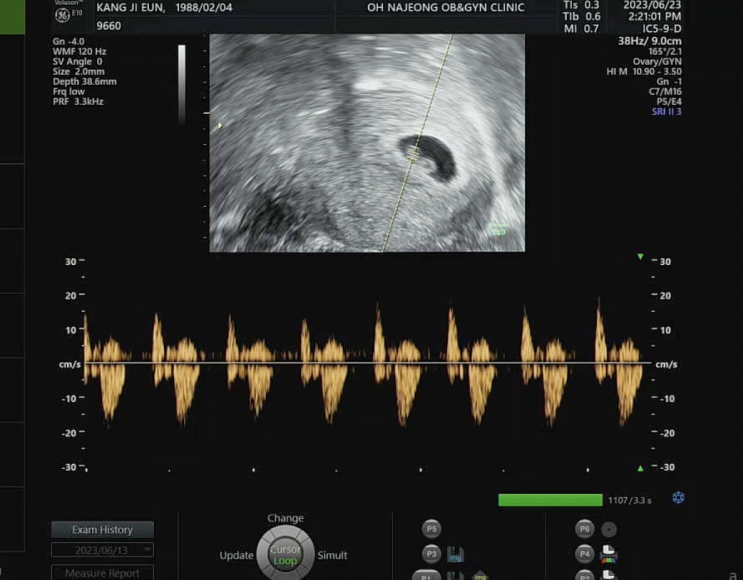

임신 6주차, 빵이 첫 심장소리 듣던 날, 입덧 시작, 입덧약 처방 (feat. 임신 후회)

임신 6주차에는 가슴 벅찬 빵이 첫 심장소리와 함께 고통스러운 입덧이 함께 찾아왔던 시기다. 심장소리는 ...